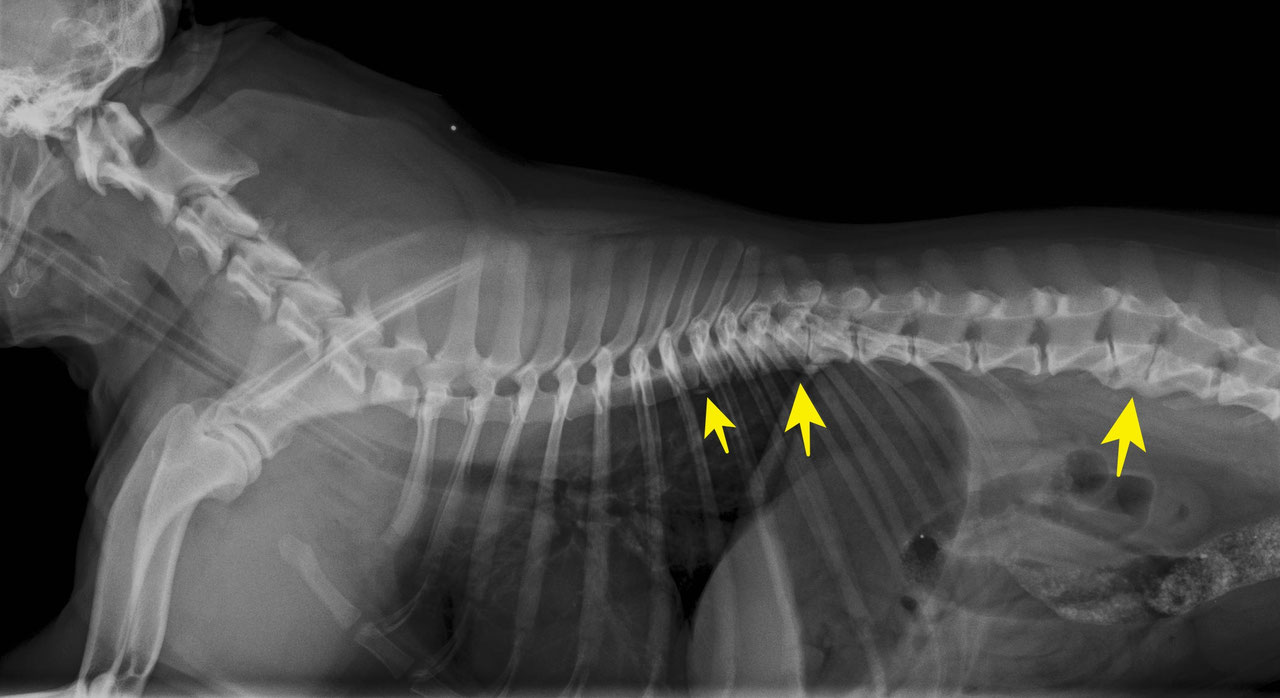

Защемление у собаки

Защемление у собаки 114 фото